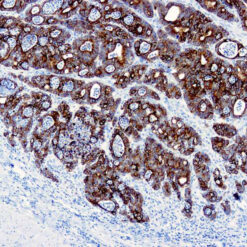

Iba1 (AIF1)

Actin-binding protein that enhances membrane ruffling and RAC activation. Enhances the actin-bundling activity of LCP1. Binds calcium. Plays a role in RAC signaling and in phagocytosis. AIF1 colocalizes with actin, and upon stimulation, translocates to lamellipodia. It is also a marker of human microglia and is expressed by macrophages in injured skeletal muscle. The gene encoding AIF1 resides in the tumor necrosis factor (TNF) cluster of genes, located in the region represented by the human major histocompatibility complex (MHC).

| Positive Control Tissue | Spleen |